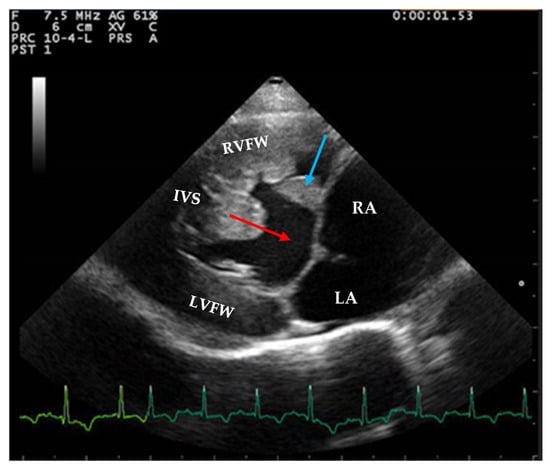

Two-dimensional echocardiography revealed significant hypertrophy of the right ventricular free wall, with a diastolic thickness of 8.7 mm, accompanied by prominent papillary muscles. The right atrium was severely dilated (maximum diastolic cranio-caudal diameter of 20.3 mm, compared to the reference value of 12 mm in healthy cats) [11]. The leaflet edges of the tricuspid valve were severely thickened. (Figure 1). The left atrium was within normal limits, with a maximum diastolic cranio-caudal diameter of 13.7 mm, compared to the reference value of 16 mm [12], while the left ventricular free wall was hypertrophic, with a diastolic thickness of 7.3 mm measured in 2D echocardiography. In the right parasternal short-axis view at the level of papillary muscles, the interventricular septum was flattened in both systole and dyastole (Figure 2). A large interventricular septal defect (VSD) was identified in both right parasternal long-axis and short-axis views, with a diameter of at least 10.2 mm measured in the long-axis view. Color-flow Doppler examination revealed a left-to-right shunt through the VSD (Figure 3), with a peak velocity of 1.3 m/s. A single large trunk was identified, originating from the base of the heart and communicating with both ventricles. Caudal vena cava was not dilated and had an inspiratory collapse.

Figure 2.

Right parasternal short axis view from a 2-year-3-month-old domestic shorthair neutered male cat underlying flattening of interventricular septum. The VSD can be observed as well (red arrow).